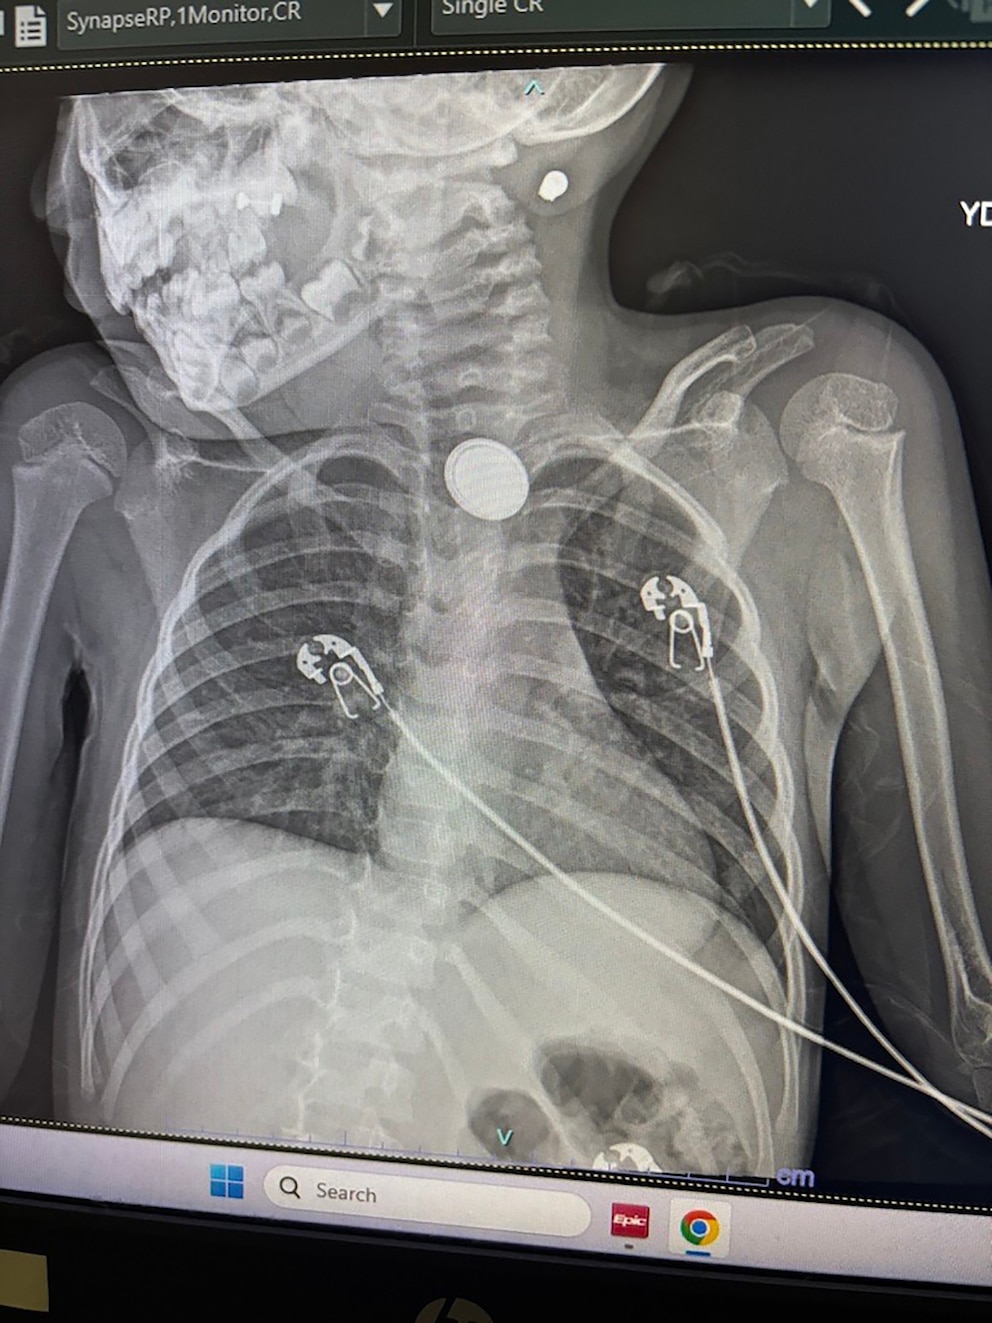

“They did an X-ray and they said, ‘Hey, we need to transport you to Children's Hospital in Aurora because we don't specialize in this. This can be a very dangerous situation,” Sandoval recounted.

At Children’s Hospital Colorado, doctors diagnosed Elana with a foreign body (button battery) ingestion.

Dr. Edwin de Zoeten, director of the Pediatric Inflammatory Bowel Disease Center at Children's Hospital Colorado, told ABC News doctors were able to remove the button battery from inside Elana’s body but the battery caused a perforation in Elana’s esophagus, which led to mediastinitis, or inflammation and subsequent infection of the mediastinum, the space in the chest between the lungs that contains tissues and organs of the chest.

Elana also needed a feeding tube, antibiotics and is under observation for a risk of further injury or complications.